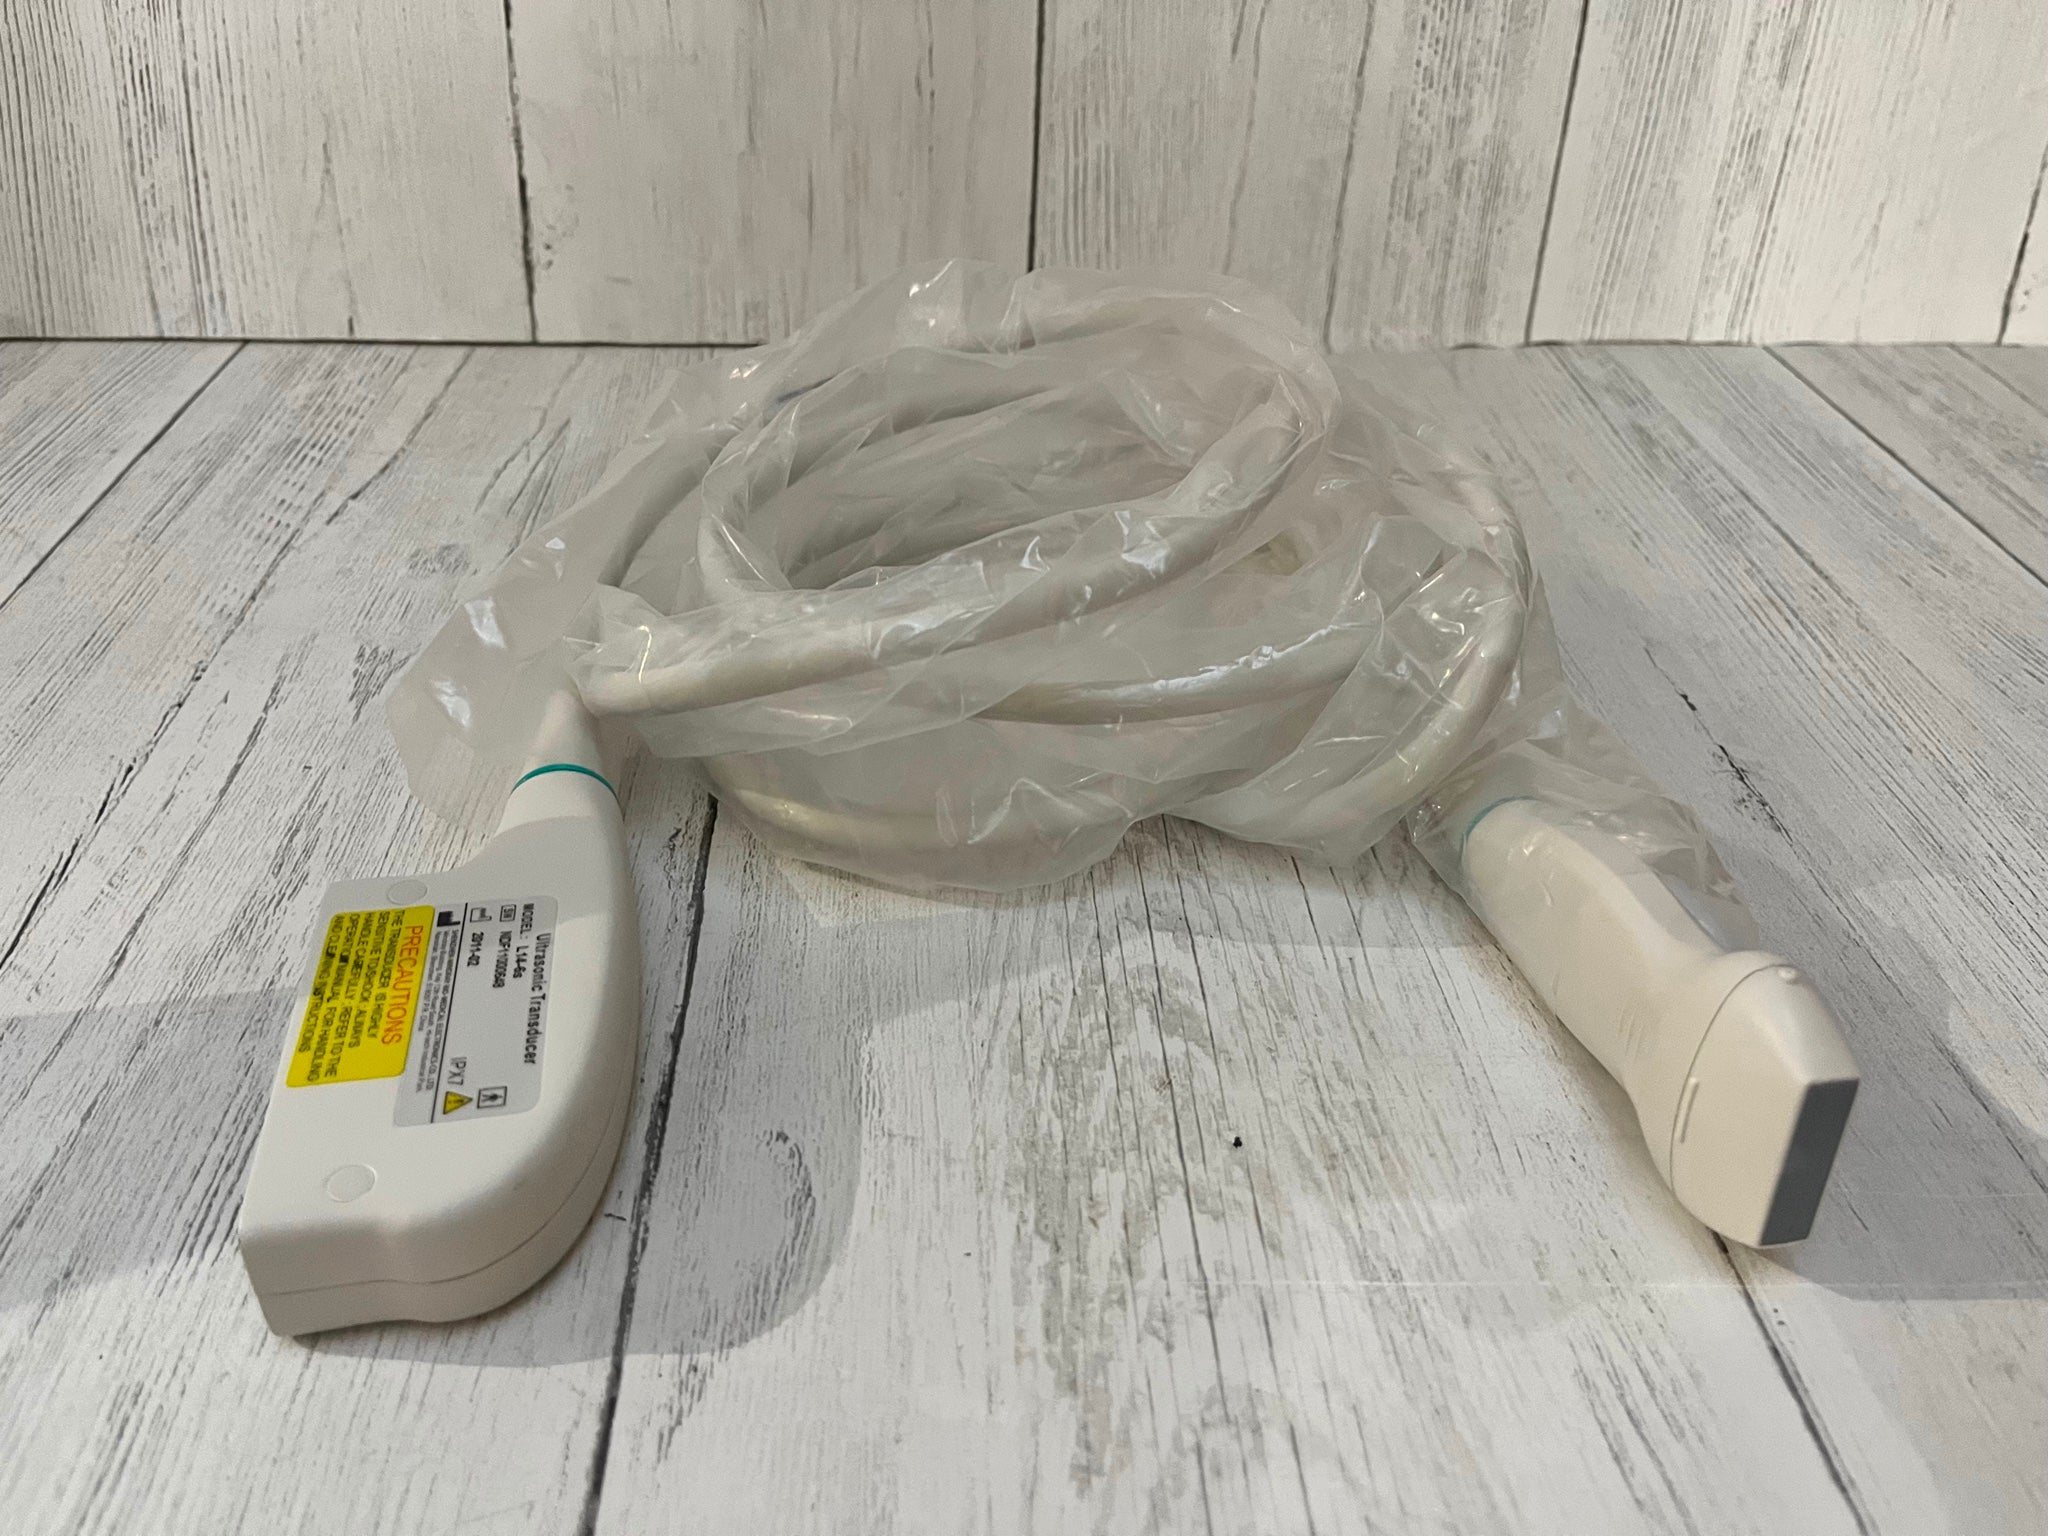

DIAGNOSTIC ULTRASOUND MACHINES FOR SALE

TOSHIBA PLT-704AT 7.5MHZ PROBE | PR5027

Sale price$ 819.18

Regular price$ 999.00